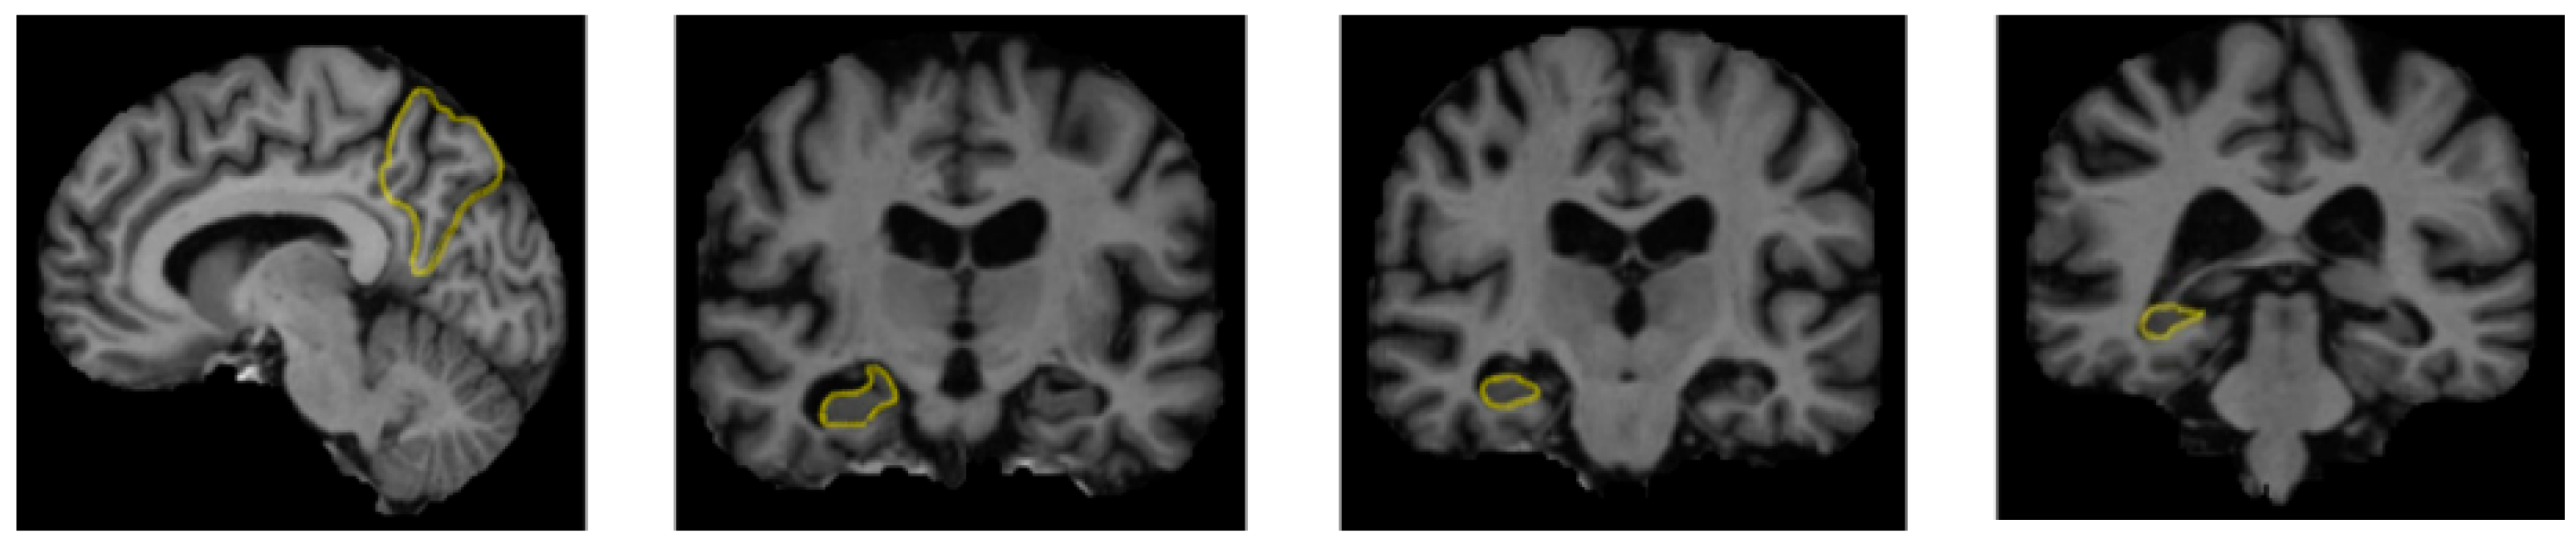

Multiple factors contribute to the development of Alzheimer’s disease, including lifestyle, cardiovascular disease, head or brain surgery, age, gender, genetic factors, infection, environmental factors, and latent diseases, such as diabetes. Spherical protein aggregates and stringy protein structures are both produced in the neuronal cell bodies of some Alzheimer’s disease-affected brain regions [24]. The spherical protein structures that Alzheimer’s disease produces are known as amyloid plaques. In Alzheimer’s disease, damaged brain tissue and deformed neuronal components are observed [25]. Figure 2 depicts the altered structure of brain tissue resulting from Alzheimer’s disease, as seen from the diminished gray matter in the brain and areas of plaque that appear in nerve neurons. Alzheimer’s disease can be diagnosed using deep learning and machine learning techniques. Most machine learning and deep learning techniques have been used to classify photographs or the regions within them, and several of these studies are reviewed collectively in this survey.

Figure 2.

Areas affected by Alzheimer’s disease in brain MRI images [Reprinted/adapted with permission from Ref. [25].